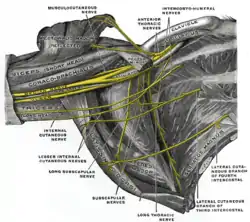

Brachial plexus with courses of spinal nerves shown

Brachial plexus with courses of spinal nerves shown Cross-section through the middle of upper arm.

Ulnar and radial arteries. Deep view. The right brachial plexus (infraclavicular portion) in the axillary fossa; viewed from below and in front.

The right brachial plexus (infraclavicular portion) in the axillary fossa; viewed from below and in front. Front of right upper extremity, showing surface markings for bones, arteries, and nerves.